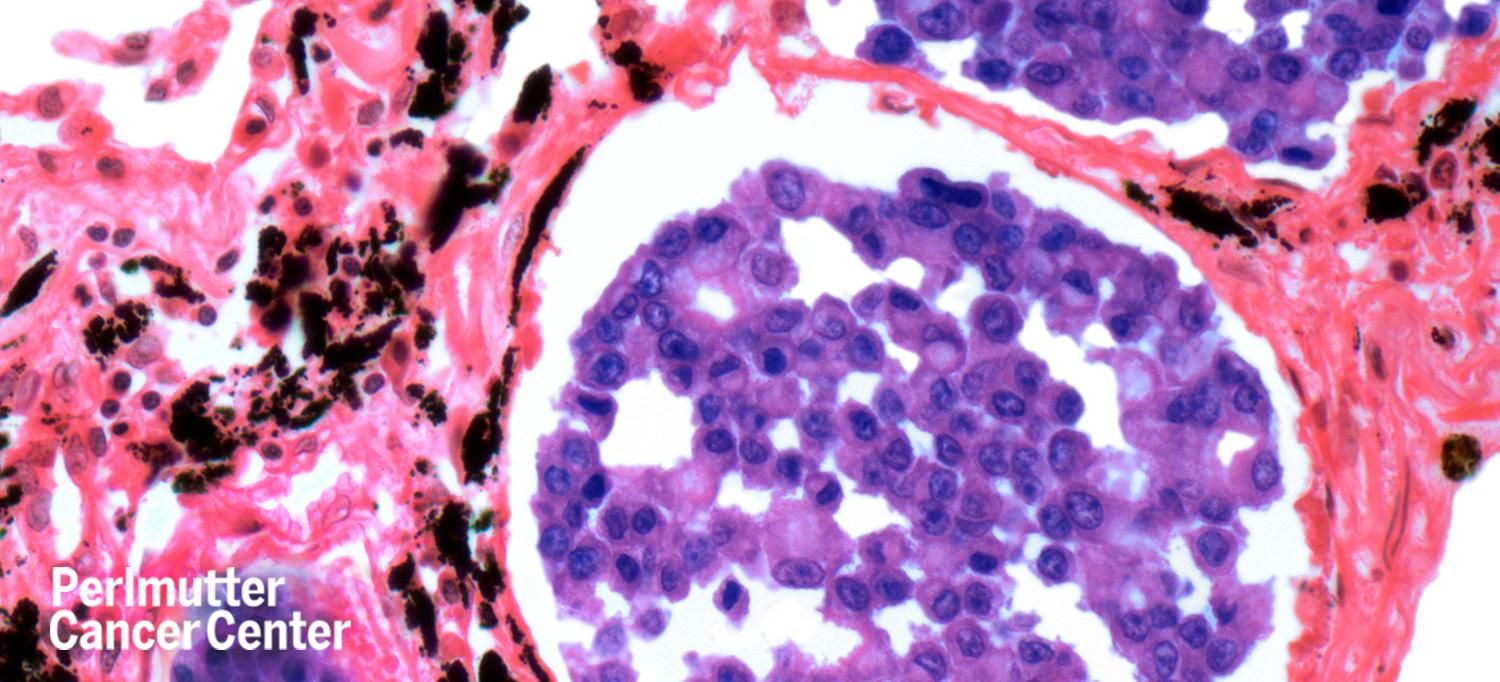

People with an aggressive form of non-small cell lung cancer that contains a rare genetic mutation called RET tend to have poorer survival rates and higher rates of brain metastases. Clinical trial results of a new lung and thyroid cancer drug called selpercatinib (Retevmo™) published in The New England Journal of Medicine showed that the drug blocks the RET mutation and stops cancer growth in more than 64 percent of people who previously received chemotherapy.

Vamsidhar Velcheti, MD, associate professor in the Department of Medicine and director of the Thoracic Medicine Oncology Program at NYU Langone Health’s Perlmutter Cancer Center, who co-authored the study, has used this treatment with many people since it first entered clinical trials. “The best thing about this drug is that the response rate is so high. I personally haven’t had any patients who did not respond to it,” Dr. Velcheti tells SurvivorNet. “It’s very exciting, but it’s still not a cure. When we treat patients with these very potent RET inhibitors, they tend to develop other gene mutations that make the drugs no longer work. We are trying to understand what kinds of mutations these patients develop that we could target with other drugs.”